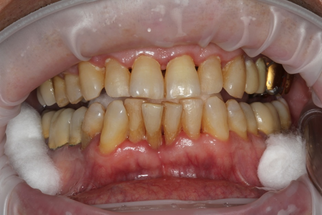

Через 30 дней после комплексного лечения с применением фотодинамической терапии у пациентов основной группы 3 отмечена выраженная положительная динамика состояния тканей пародонта по сравнению с исходным уровнем (Рисунок 15). Все пациенты отмечали снижение кровоточивости десен при чистке зубов, исчезновение неприятного запаха изо рта, гноетечения из ПК. Объективное обследование показало, что у всех пациентов отсутствовали признаки активного воспаления в тканях пародонта (отек и гиперемия), существенно снизилась степень кровоточивости десны, прекратилась активная экссудация из пародонтальных карманов.

| до лечения | через 30 дней после лечения |

| Рисунок 15. Динамика состояния тканей пародонта у пациента с ХГП тяжелой степени через 30 дней после комплексного консервативного лечения с применением фотодинамической терапии. | |